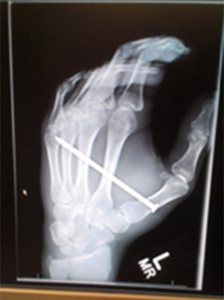

The 3.5” nail was embedded completely in his palm. The cuff of his sweatshirt was nailed to the base of his thumb. He could see the point of the nail through the skin on the back of his hand between his ring finger and his pinkie.